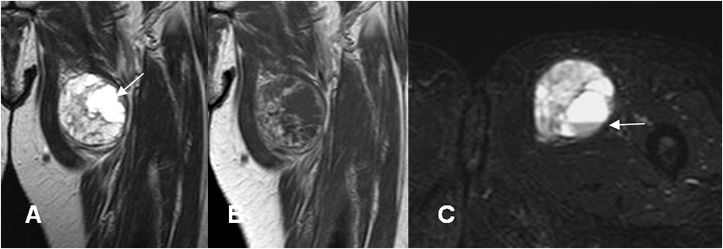

Fig 176. Neurofibroma.

A: RM coronal en T1 simple y B: RM coronal en T1 con contraste. Imagen fusiforme que sigue la topografía del nervio ulnar, con realce del contraste secundario a neurofibroma.